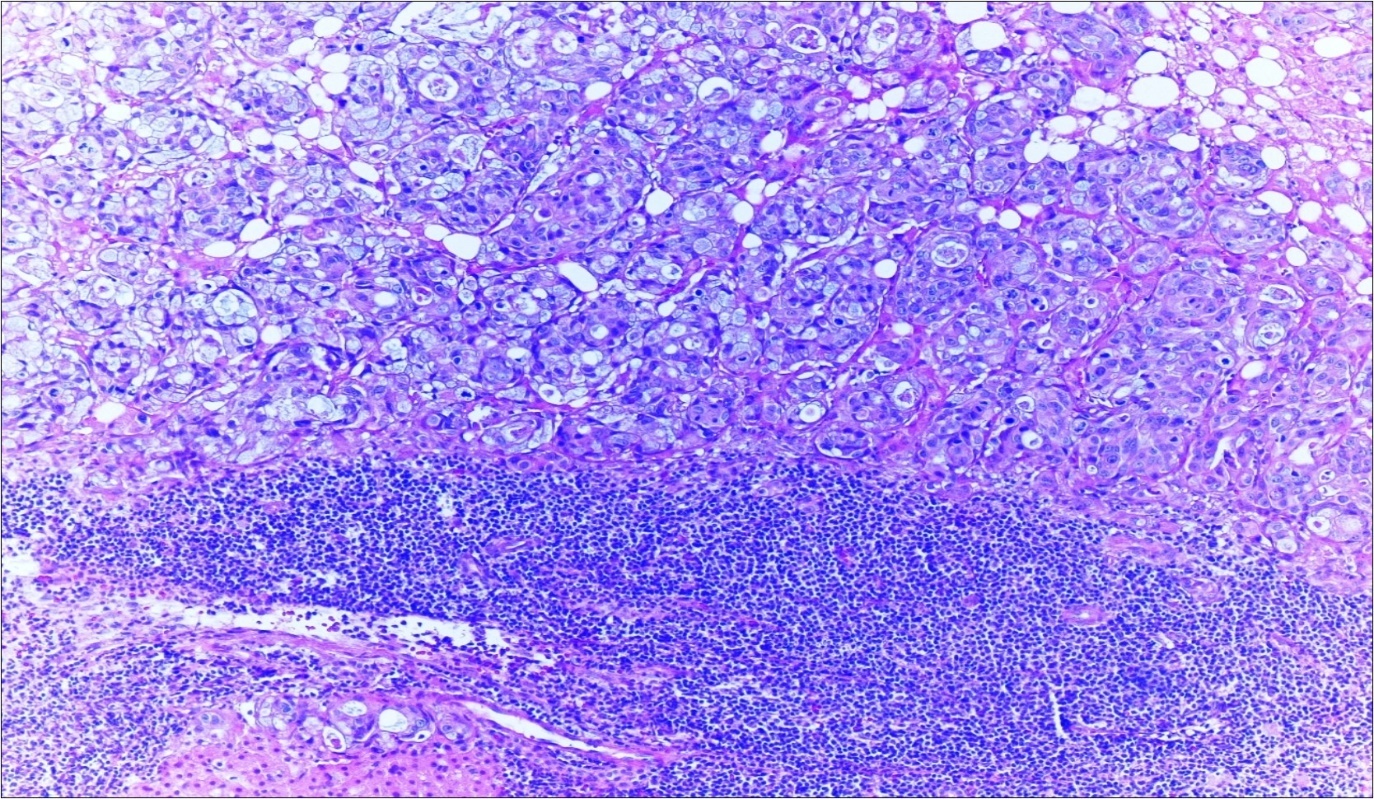

A 63-year-old woman presented to the Department of General Surgery as an outpatient with abdominal pain. Physical examination showed the signs of acute appendicitis and appendectomy was performed. During microscopic examination, a small focus of atypical monotonous lymphoid cell population was seen and the material was sampled totally. The pathological examination revealed MALT lymphoma (Figure 1), with diffuse positivity of cluster of differentiation (CD) 20 (Figure 2), CD 79a and B-cell lymphoma (Bcl- 2) (Figure 3) with just a few CD3 positive lymphoid cells. However, no evidence of adenocarcinoma was found in the appendectomy specimen. After the diagnosis of lymphoma, a complete colonoscopy was planned and this revealed a solid tumoral mass in the caecum measuring 5x4x4 cm. Computed tomography of the abdomen and pelvis revealed mesenteric lymphadenopathy associated with a mass in the caecum with multiple nodules in liver consistent with metastasis (Figure 4). Frozen sections were not obtained since the treatment method would not be affected. The patient underwent anterior resection with regional lymphadenectomy, with the pathological assessment of the resected specimen revealing a collision tumor consisting of a poorly differentiated adenocarcinoma extending through the muscularis propria with MALT lymphoma (Figure 5). Microscopic evaluation of the 11 regional lymph nodes in the mesentery of the resected colon and liver biopsy showed diffuse infiltration of MALT lymphoma with metastasis of adenocarcinoma (Figure 6). According to immunohistochemistry, atypical lymphocytes were positive for CD 20, Bcl-2, and negative for CD3, CD5, CD10, CD23, Bcl-6, terminal deoxynucleotidyl transferase, and cyclin D1. The proliferation fraction (MIB-1 immunostaining) was approximately 20%. The morphological and immunohistochemical findings were used to confirm the diagnosis of synchronous presentation of MALT lymphoma and colon adenocarcinoma within the caecum, mesenteric lymph nodes and liver metastases.

Figure 5.Adenocarcinoma with MALT lymphoma infiltration of colon (h&e;200)